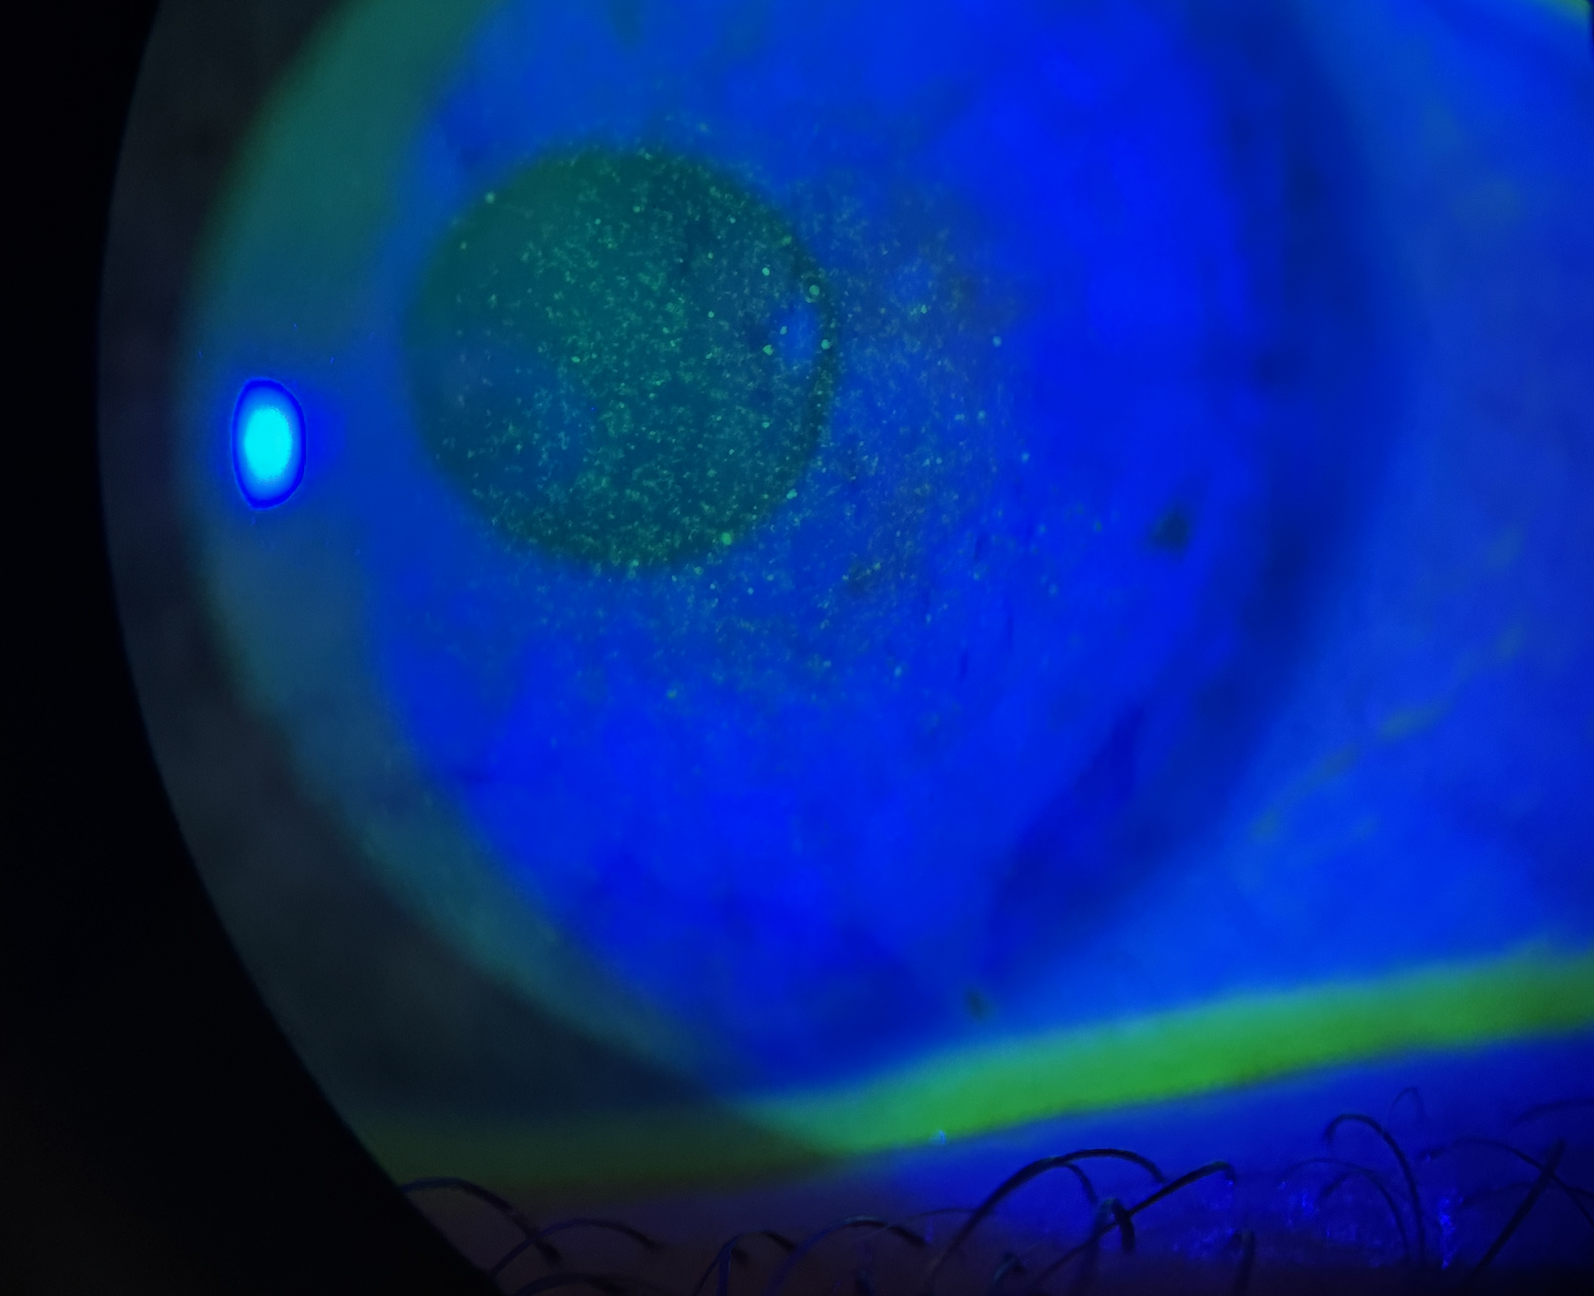

Les allergies oculaires, bien que bénignes dans la plupart des cas, peuvent altérer le quotidien. Elles concernent environ 15% de la population mondiale et sont souvent liées à un terrain atopique. Les allergènes les plus fréquents sont les pollens, les acariens, les poils d’animaux, les produits cosmétiques, les collyres, etc. Les allergies peuvent être aiguës ou chroniques. Les symptômes sont marqués par des démangeaisons, une rougeur, un larmoiement, une sensation de corps étranger et de brûlure. Une prise en charge adaptée, combinant prévention et traitements, permet de soulager les symptômes et d’améliorer la qualité de vie des patients. Les frottements oculaires doivent être évités puisqu’ils entretiennent la sensation de prurit et sont aussi responsables de complications oculaires (inflammation, kératocône, etc).